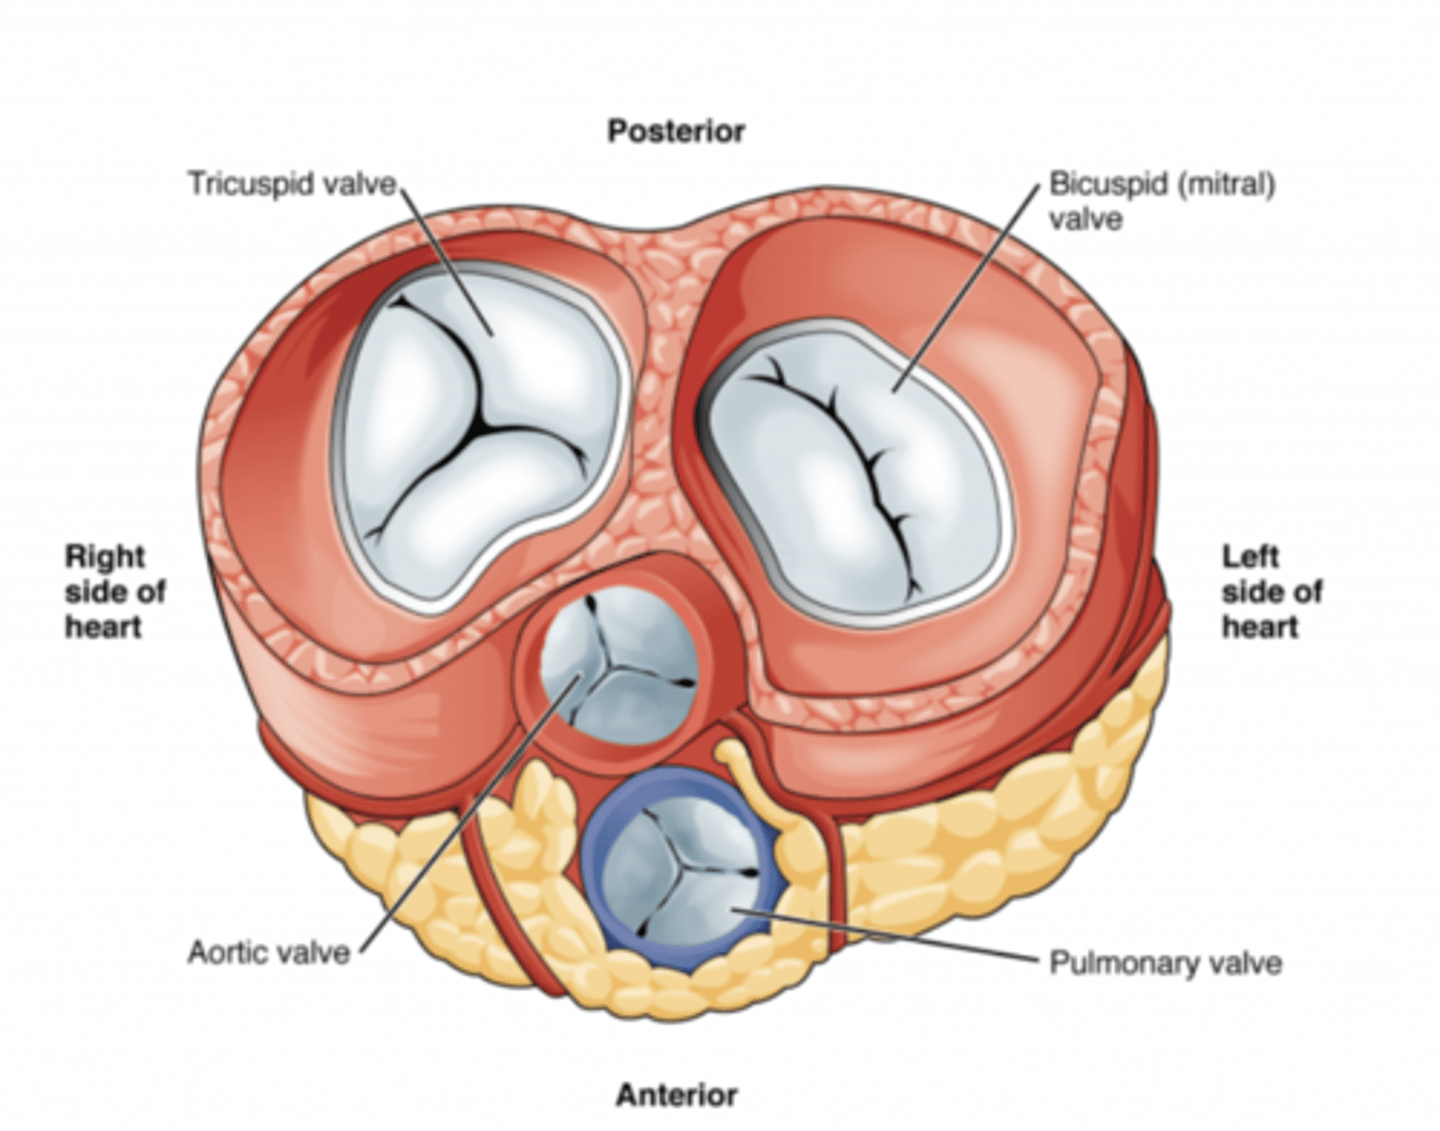

What are the valves separating atrium and ventricle?

. Tricuspid valve (right atrioventricular valve, 3 cusps)

. Mitral or bicuspid valve (left atrioventricular valve, 2 cusps)

AXIAL VIEW OF THE HEART

What are the 3 cusps of the tricuspid valve?

Anterior

Posterior

Septal

What are the four valves in the heart?

Tricuspid

Mitral or bicuspid

Pulmonary

Aortic

What valves are assuring the AV unidirectional flow?

Tricuspid (right)

Mitral or bicuspid (left)